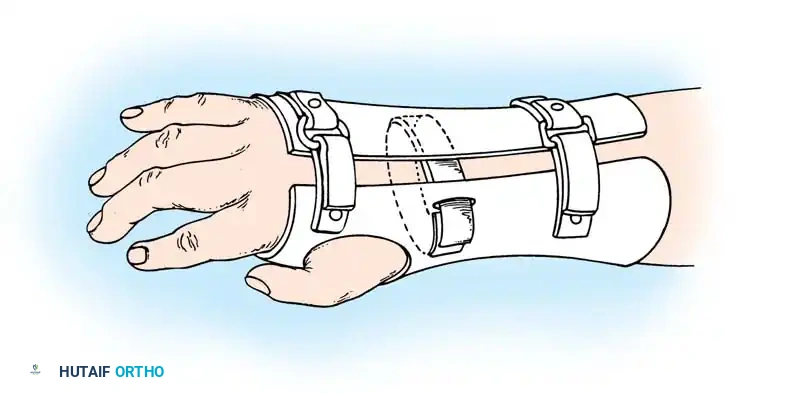

Fig. 76-3 A and B. Early fitting of a passive prosthesis in a child with a congenital forearm amputation is critical to encourage incorporation of the prosthesis into the child's body image.

1. 3 to 6 Months (Sit to Fit): A passive plastic mitten prosthesis is introduced once the child achieves independent sitting balance. This provides stability during sitting and assists in pulling to a stand.

2. 12 to 18 Months: The passive mitten is exchanged for an actively opened, plastisol-covered split hook. A Child Amputee Prosthetic Program (CAPP) terminal device may be substituted. Training with the functional device begins immediately.

3. 2 to 4 Years: A myoelectrical prosthesis may be considered. Studies have shown these to be highly useful and appropriate for preschool-aged children, offering superior cosmesis and intuitive grip control.